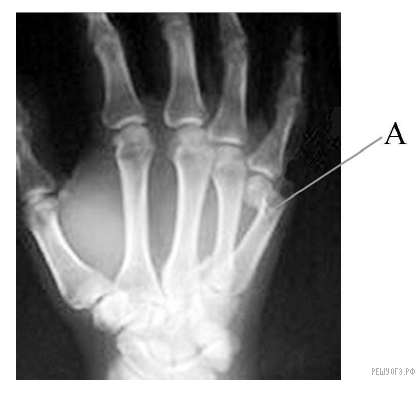

Как называют повреждение, обозначенное на рентгеновском снимке буквой А?

На рентгеновском снимке виден перелом — нарушение анатомической целости кости вследствие травмы.

Правильный ответ указан под номером 1.